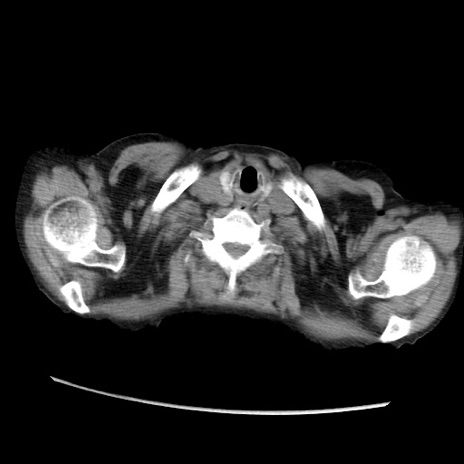

症例31(横断像)

【症例】80歳代 女性

【主訴】腹部膨満感

【現病歴】他院にて肝硬変にてフォロー中。1週間前から便秘、腹部膨満感、臍部腫瘤あり受診となる。

【既往歴】肝硬変

【身体所見】腹部膨隆あり、皮膚変化なし、疼痛なし。

【データ】WBC 4600、CRP 0.25